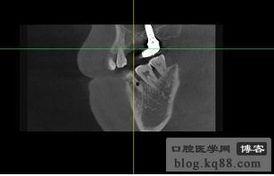

1. 诊断鼻骨骨折:通过对比正常鼻骨CT图片和患者的CT图片,医生可以判断患者是否患有鼻骨骨折。